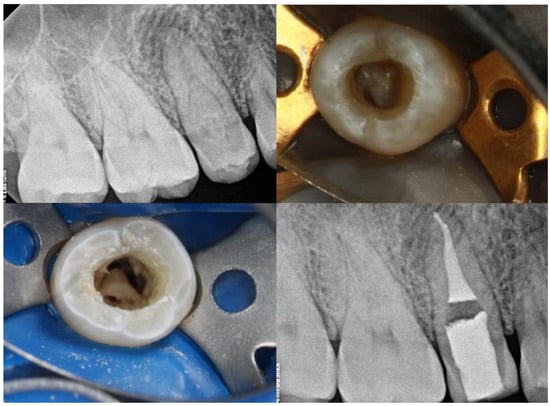

| Type IIIa/IIIb | High risk of periapical/periodontal infection | CBCT essential to determine anatomy and extent | Selective treatment of infected invagination if pulp unaffected Often requires surgical access and debridement Orthograde or retrograde obturation with biocompatible materials Combined endodontic and periodontal approach in complex cases | Prognosis depends on anatomical complexity and extent of infection Long-term monitoring essential due to risk of reinfection |